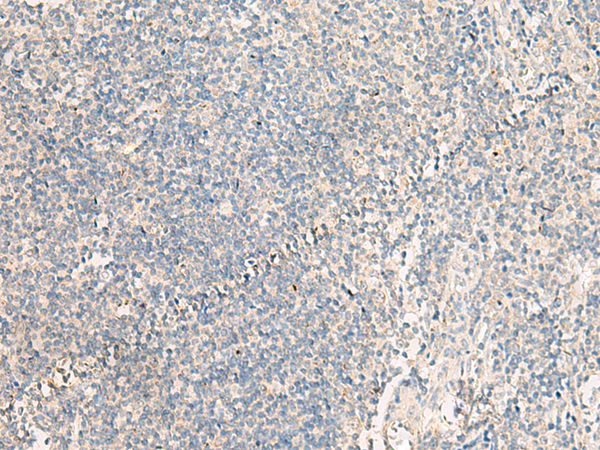

分类: 科研抗体货号: P13548别名: IHABP4; IHABP-4; Ki-1/57; SERBP1L应用: IHC反应种属: Human, Mouse, Rat